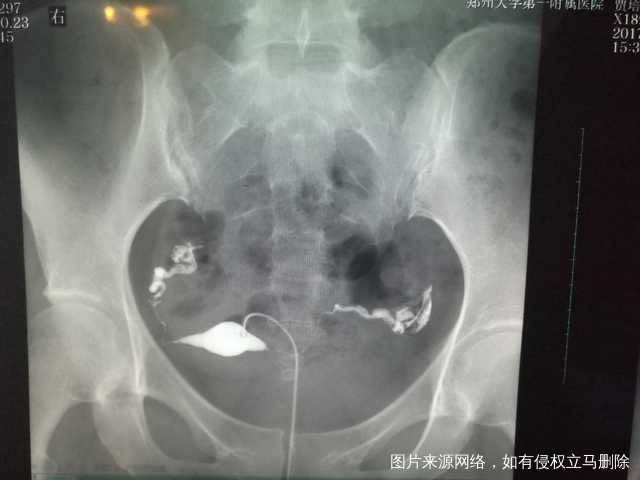

做完输卵管造影第六天了小腹还是感觉沉甸甸的如

可以热敷腹部,如果有发热,腹痛加剧,白带量多,有异味,随时就医